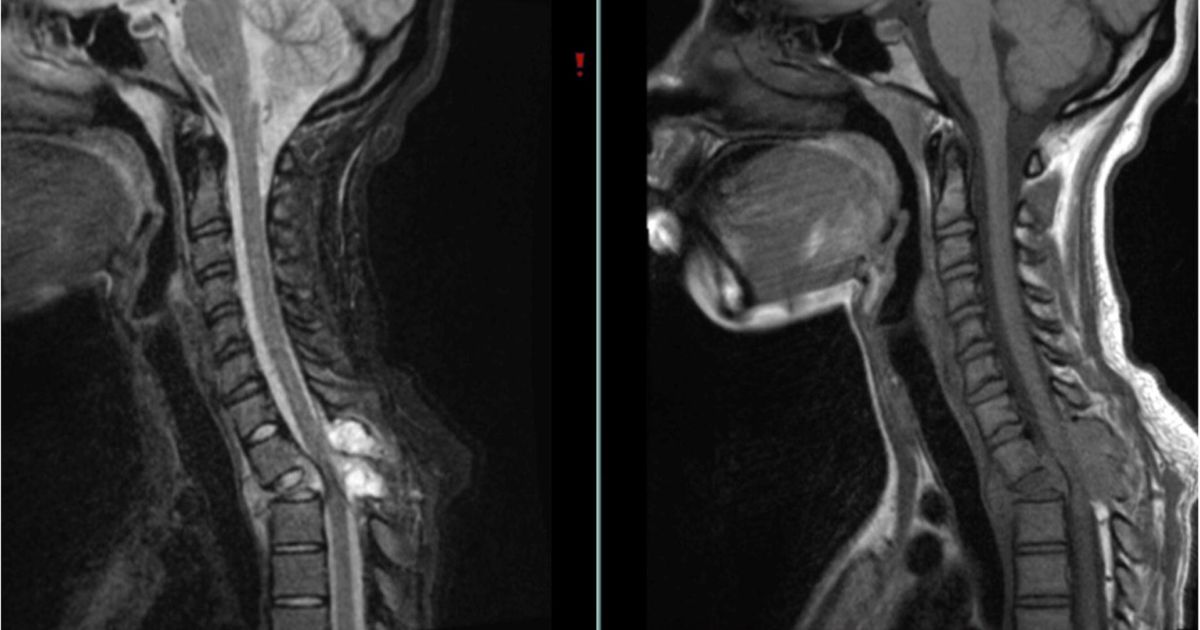

Bệnh nhân có thể được yêu cầu chụp cộng hưởng từ (MRI). Phương pháp này giúp đánh giá chính xác cấu trúc bên trong của u, xác định mức độ lan rộng và đặc điểm dịch trong nang.

Các bác sĩ sẽ nghi ngờ bệnh nhân có khối u nang trong xương nếu xuất hiện các bất thường trên phim chụp như:

• Hình ảnh dịch xuất hiện do máu trong nang có tỷ trọng khác nhau, tạo thành các lớp phân tầng rõ rệt.

• Trên ảnh T1, u thường có tín hiệu giảm; trên ảnh T2, tín hiệu tăng mạnh, thể hiện rõ các khoang dịch khác nhau.

• Có thể thấy phù nề mô xung quanh hoặc các vách ngăn mỏng chia nhỏ khối u.

Ngoài ra, điểm mạnh của MRI so với X Quang nằm ở chỗ giúp phân biệt u nang xương phình động mạch với các bệnh lý ác tính khác như sarcoma xương dạng giãn mạch – dạng ung thư xương có đặc điểm hình ảnh tương tự nhưng nguy hiểm hơn nhiều.

Dưới phim chụp MRI, khối u được quan sát rất rõ ràng